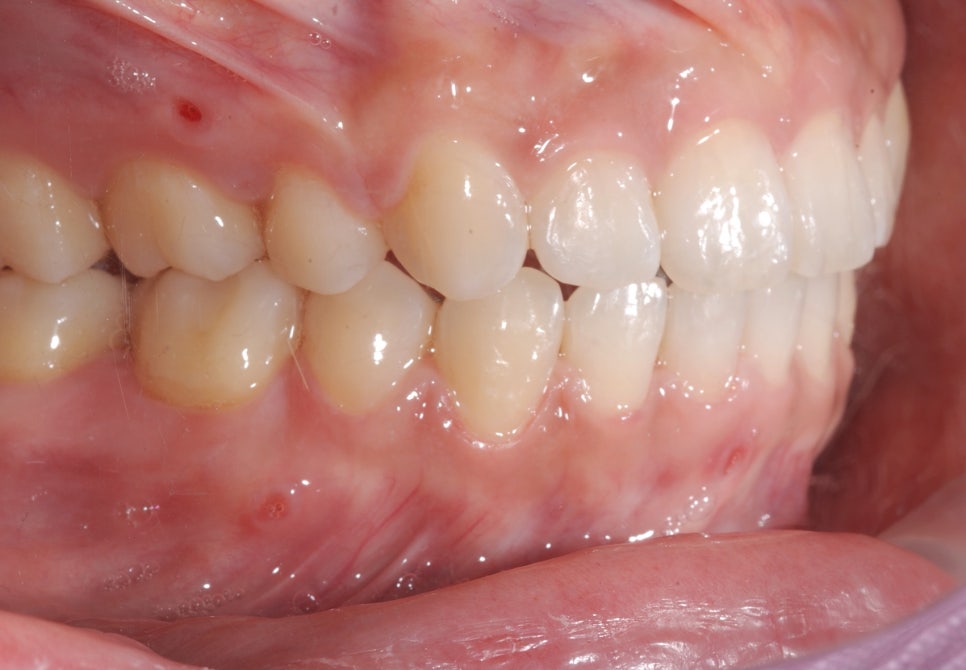

Around 12 months later, the extraction spaces had closed, and you can see that the teeth were moving inward well.

The treatment period was about 1 year and 6 months,

and before treatment, the lower jaw looked more prominent when speaking or smiling,

after treatment, it changed to a much softer and more natural appearance.